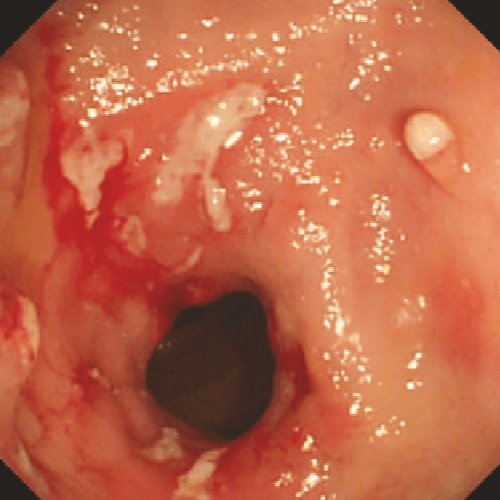

Rutgeerts i2

bolezn_krona.png

i2

>5 афтозных язв с нормальной слизистой оболочкой между ними ИЛИ протяженные участки здоровой слизистой оболочки между более выраженными изъязвлениями ИЛИ поражения, ограниченные подвздошно-толстокишечным анастомозом